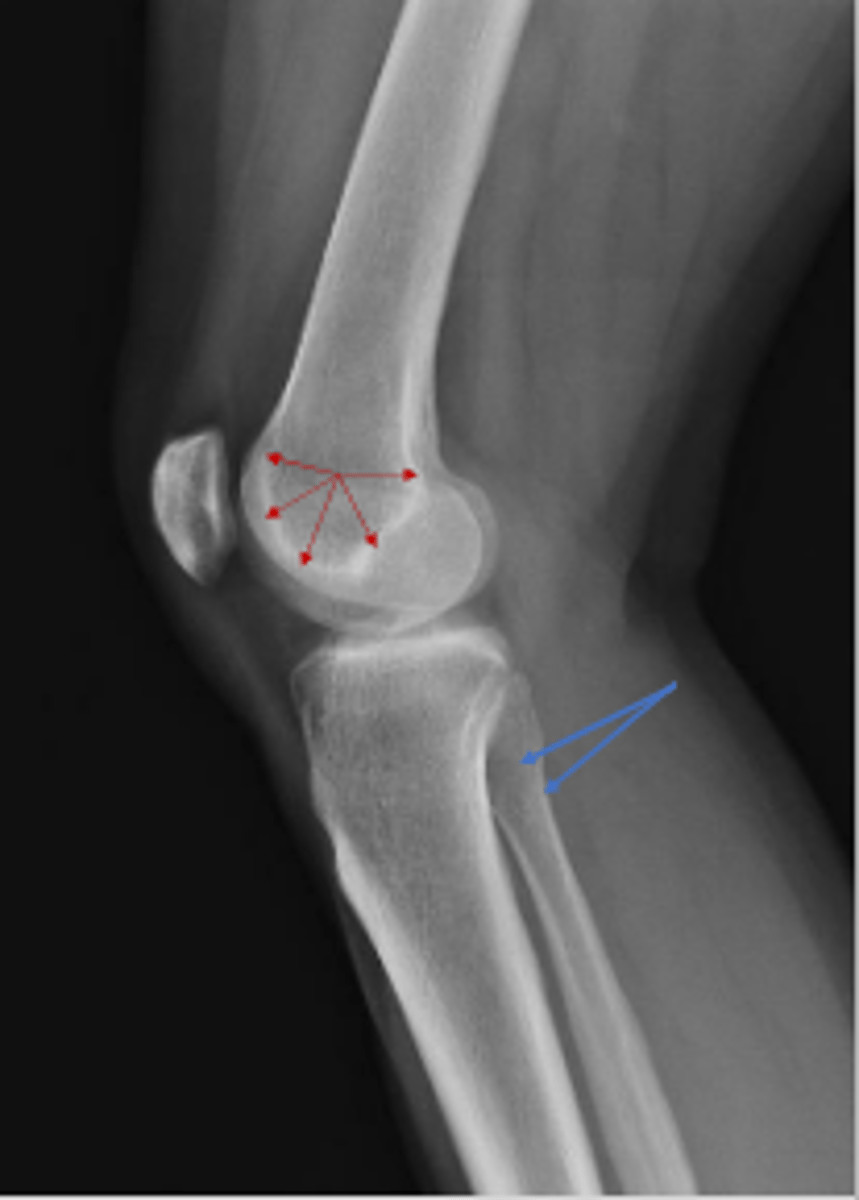

The right medial & tibial plateaus and the right

medial and lateral condyles right knee

What is outlined?